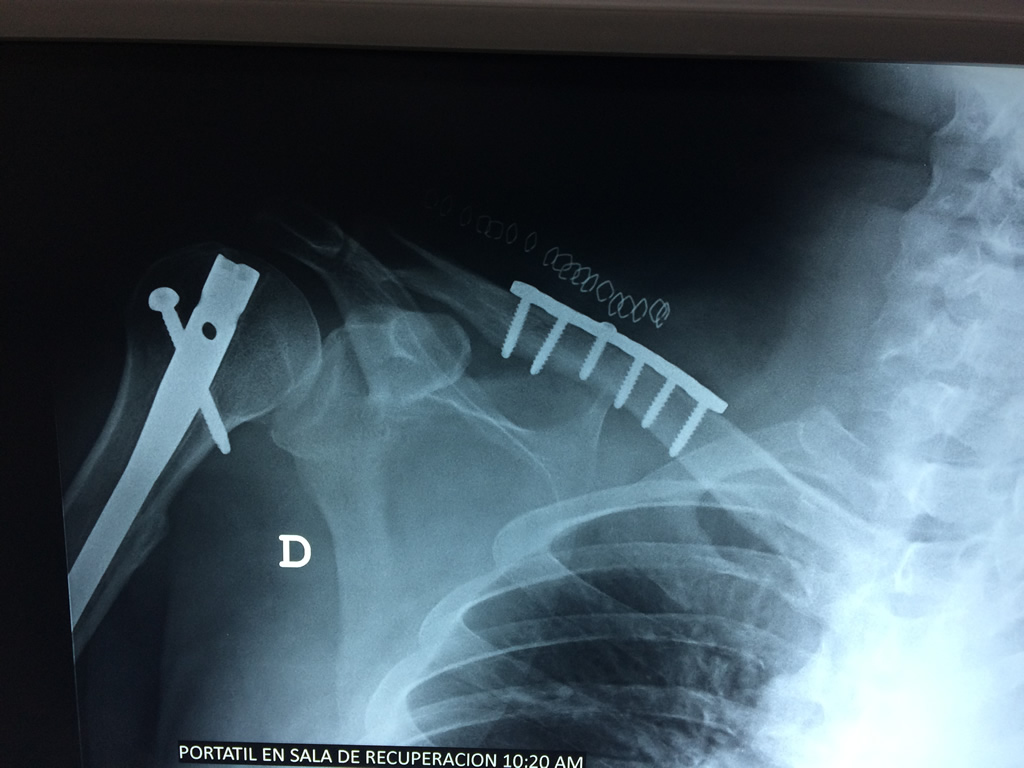

Clavicula 3

Detail Download